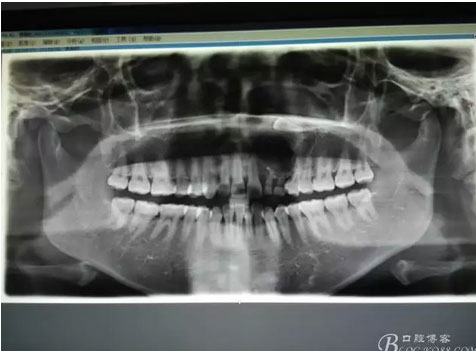

圖1。術前的CBCT影像檢查:22位于鼻底下方,23位于24、25的根方。左側乳Ⅱ、Ⅲ根方顯示囊性改變,囊腔內大量致密鈣化團塊,密度高。

圖18.摘除囊腫后遺留的巨大骨腔

圖21.術中拍全景片,看是否有牙瘤殘留,發(fā)現左側乳Ⅱ根尖區(qū)還有少量致密鈣化物,建議拔除左側乳Ⅱ、,患者要求保留兩個乳牙。經協商,遺留極少量鈣化物,不影響整體愈合。通過骨腔探查,發(fā)現左側乳Ⅱ、Ⅲ根尖區(qū)未破壞,骨壁尚完整。同意遺留部分鈣化物。有點缺憾,為了保留乳牙和患者的美觀及功能。定期觀察遺留部分的發(fā)展變化